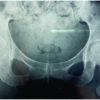

A 56-year-old man with a history of bilateral hip osteoarthritis due to Perthes’ disease and mild alcoholic liver disease presented to our hospital complaining of worsening right hip pain and difficulty in walking for the 3 previous weeks. On presentation, his temperature was 38.7°C, and laboratory results revealed a white blood cell count of 19.2 × 103 cells/L and C-reactive protein level of 43.56 mg/dL. The right hip experienced extreme pain on mobilization. Radiographs showed bilateral hip osteoarthritis due to Perthes’ disease (Fig. 1). Contrast-enhanced computed tomography showed fluid retention from the iliac muscle to around the right hip, and magnetic resonance imaging of the right hip was suggestive of septic arthritis (Fig. 2). Three-phase bone scintigraphy showed increased activity in all phases (Fig. 3).